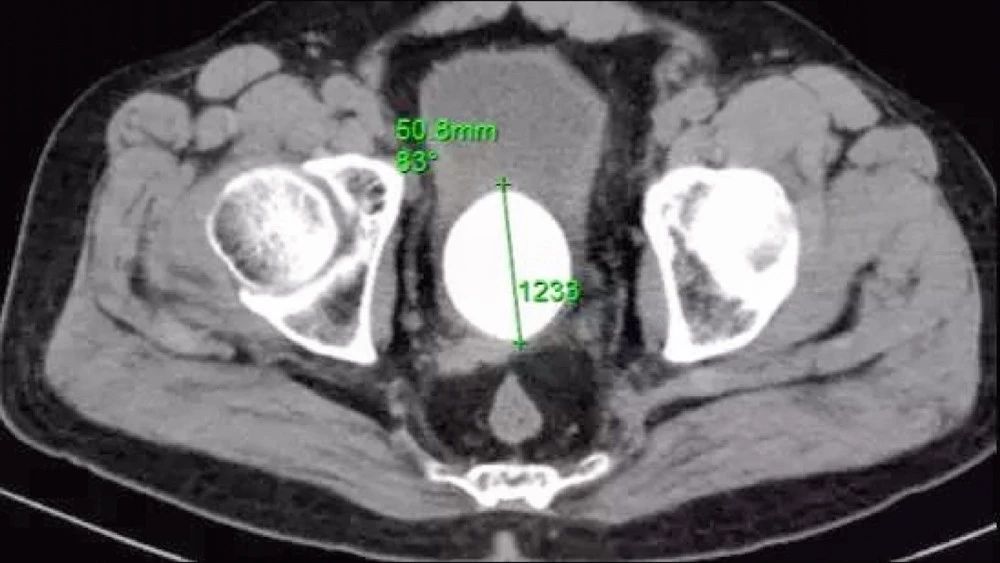

近日,漳州市第三医院泌尿外科接诊了一位患者,此次手术,从膀胱里取出了一个直径5厘米如同鸡蛋大小的石头。

漳州市第三医院泌尿二科主任韩聪祥表示,这么大的石头以前比较常见,但是目前比较少见。